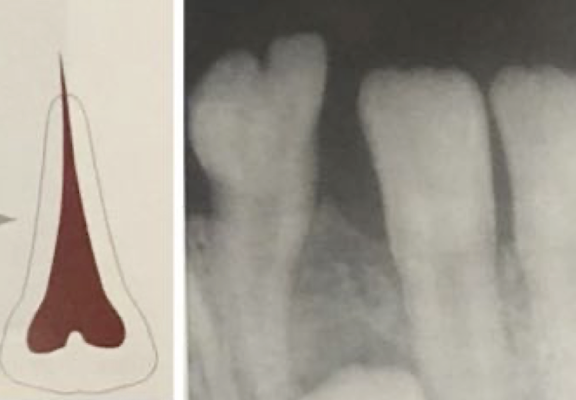

What is the purple line pointing to?

a mesioden